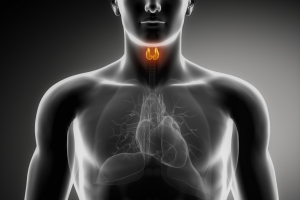

Total T3 is a blood test that evaluates thyroid gland functions. This test is also used to monitor the effectiveness of treatment of a thyroid disorder.